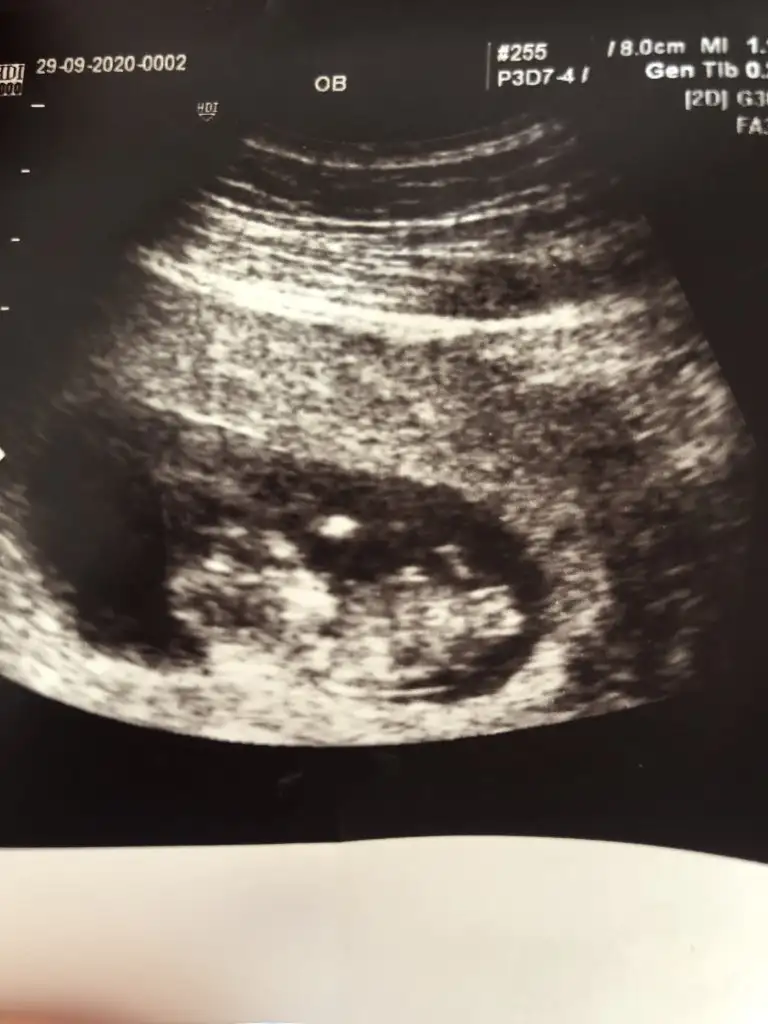

Yanlış yere etiketlemisim Bu iste Mely15Banada tahminde buluna bilir misiniz acaba kizlar

Kaç haftalık büyük sanki USG 11 12 13 haftalar olmalı sanki sanki kız gibi tekrar USG paylasinBana da tahminde bulunabilir misiniz acaba

Gönlünüz kizmi diyorGözükmüyor ama bence kiz canim bide sne bak